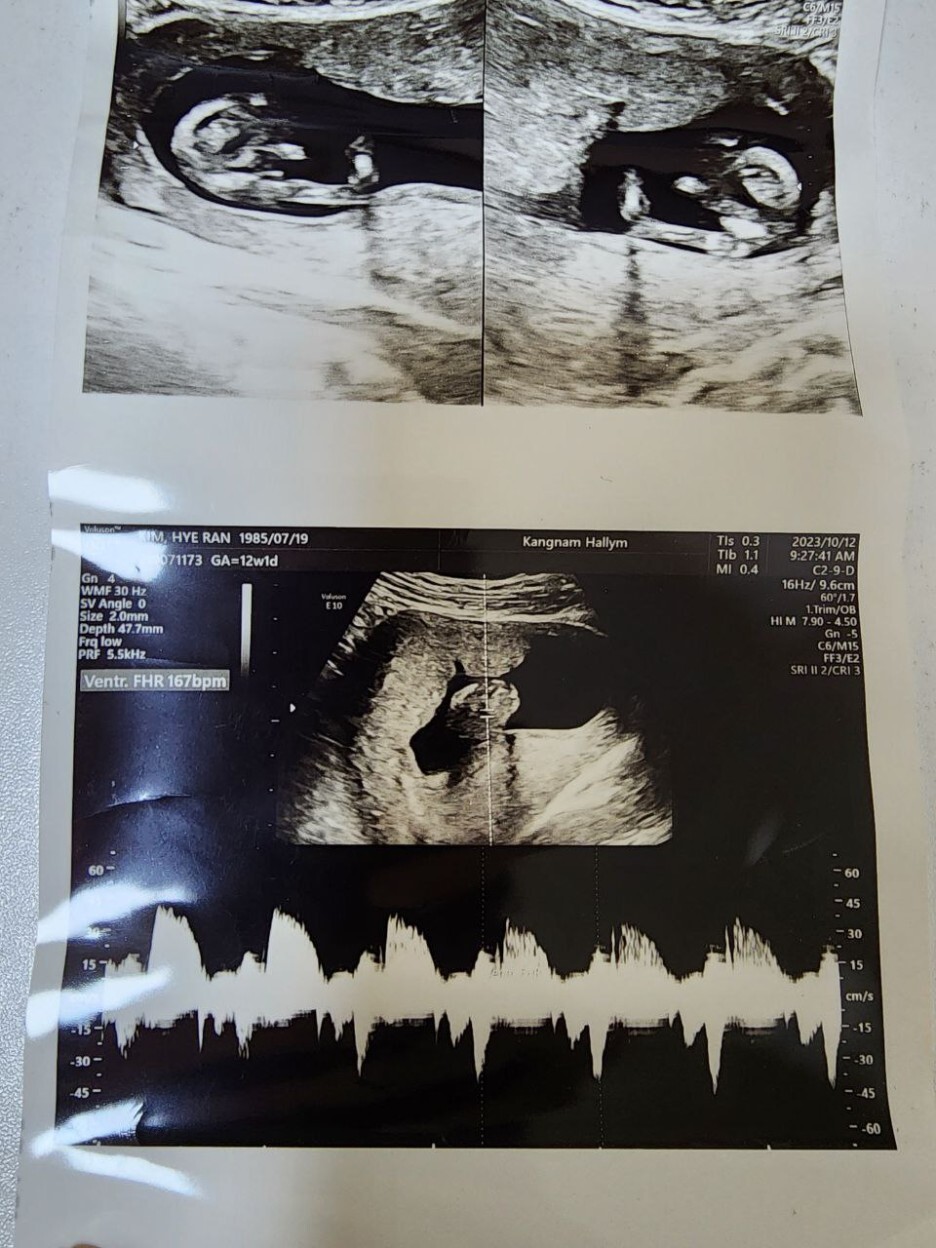

2023년 10월 12일(목요일)

FHR(Fetal Heart Rate, 심장박동 수): 167bpm

소견: 1차 기형아 검사 목 투명대랑 콧대 모두 정상으로 나옴 / 니프트(NIFT) 피검사함(결과는 2~3주 뒤 나옴)

이번 방문에서 초음파로 1차 기형아 검사 및 니프트 검사를 했다.(피 1통 뽑음) 결과는 다음번 진료 때 알려주신다 하는데 사실 초음파 상으로 이상 소견이 없어서 정상으로 나올 확률이 높다고 하셨지만 노산인 나는 걱정되는 마음에 비싸지만 했다.(니프트 비용: 한림대학교 강남성심병원 2023년 10월 12일 기준 605,000원)